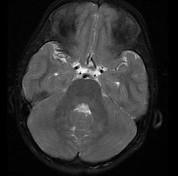

问题 女,13岁,皮肤有多发结节和多发棕色素斑,MR表现如图,最可能的诊断是()

选项 A.脸颜面血管瘤病 B.结节性硬化 C.神经纤维瘤病 D.听神经瘤 E.松果体瘤

答案 C